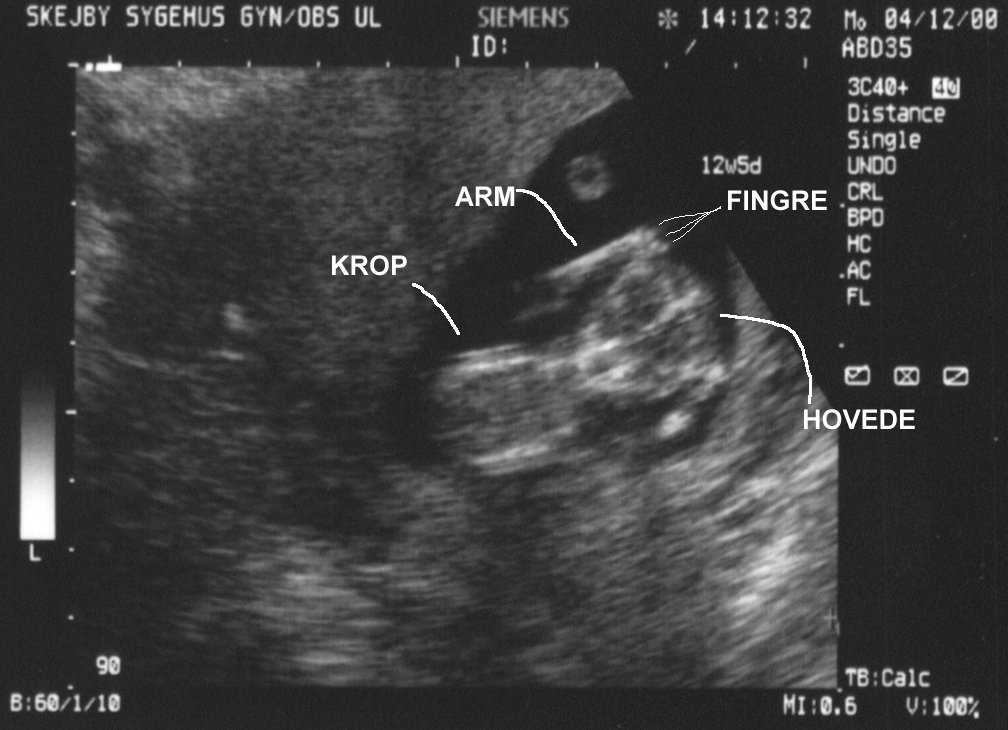

Scannings at the 12th and 19th week of the pregnancy.

Full picture from scanning in the 12th week. Lots of life and movement in there. Same picture, but with explanations. It takes a bit of practice to see anything on these images. Facial shot - looks eerie, but she was looking all the time curiously at the scanner. Really detailed - even though she's 12 cm from head to butt here. Same picture, but with explanations. Sorry, it's all in danish.